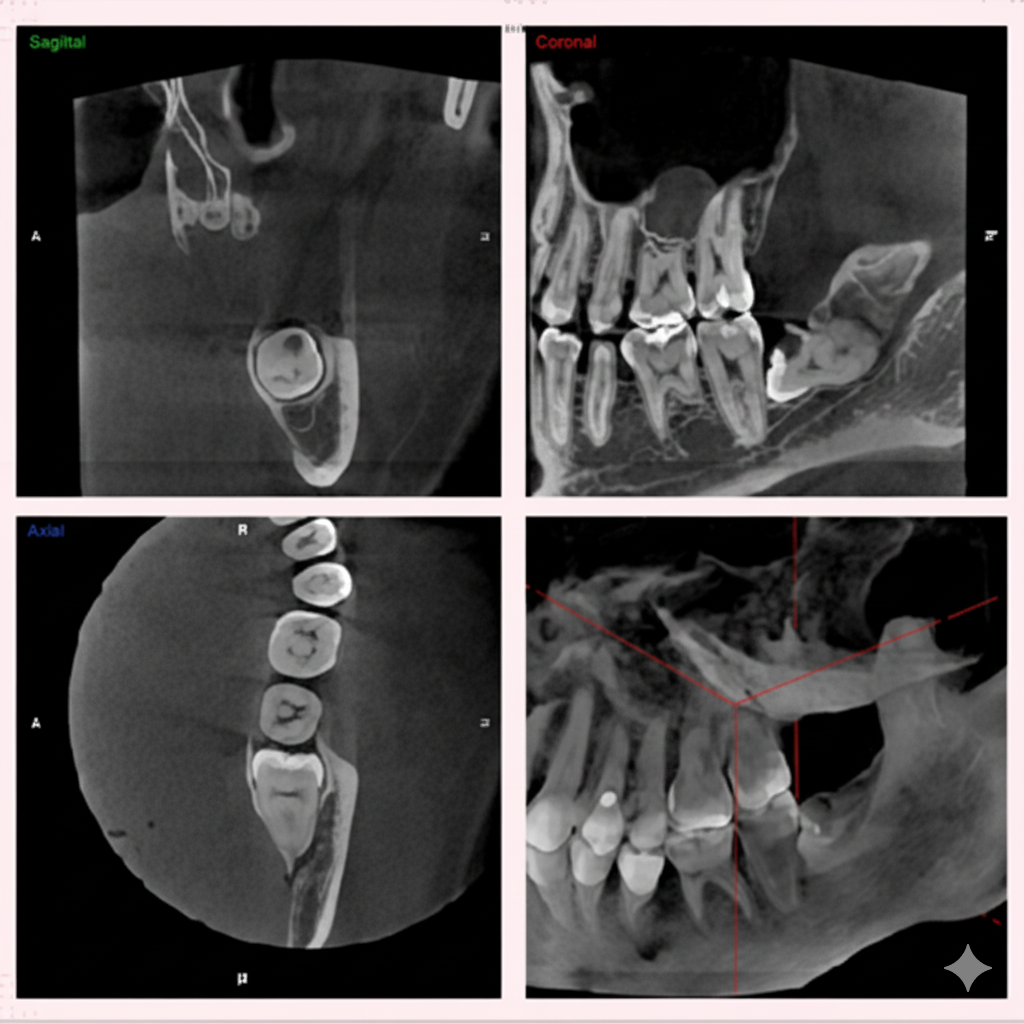

インプラント治療では、CTの画像から埋入する部位の骨の状態(質や厚み、高さ、形態など)を正確に読み取り、そこから治療計画を立てることが出来ます。歯科用CTでの撮影画像をもとに、的確な治療計画を立てることは、安心な治療への第一歩です。また三次元の立体画像から、神経などを避けた安全な位置、方向、深さを決定し埋入する事が可能となり、より安心・安全な治療を提供する事が出来ます。

歯周病は、細菌感染による骨の破壊が起きる病気であるため、骨の破壊の程度などをよりリアルに見て判断することができます。また、骨の状態からおおよその 歯の寿命を積算することも可能です。従って、非常に予知性の高い治療が行えます。 歯科用CTを使った検診を行うことで、歯を支えている骨の状態などを直接的に見ることが出来ます。

歯の神経や根っこに潜む細菌をきれいに取り除く、根管治療。CT画像では、根の本数や神経の入っている管の方向、そして位置を正確に把握することができます。また、細かい根の破折も発見できるので、早期治療が可能になります。

歯科用CTを親知らずの抜歯に利用することで、神経までの正確な距離や、周囲の炎症の程度、病巣の有無や大きさ、位置なども判断・考慮して、治療を行うことができます。また埋伏歯などの位置なども精密に判断できるので、余分な切開や骨の切削などを避けることができます。